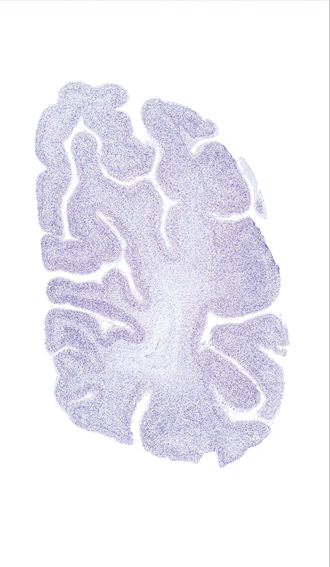

Hi-Resolution Sections · Cells (Nissl Staining) · Virtual Microscopy

Frontal sections (Nissl) from the Atlas Brain:

Slice ID:

r4-1322

Plate NR:

63

Position:

72,5 mm